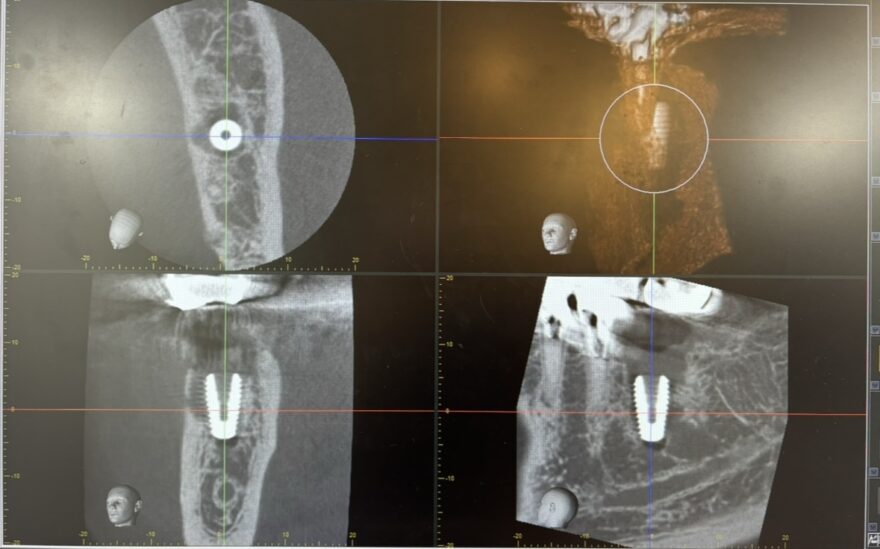

CTで位置をしっかり確認します

インプラントがどの位置に、どのように入っているかを

CT撮影でしっかり確認します。

実際の画像を見ながらご説明しますので、治療後も安心していただけます。